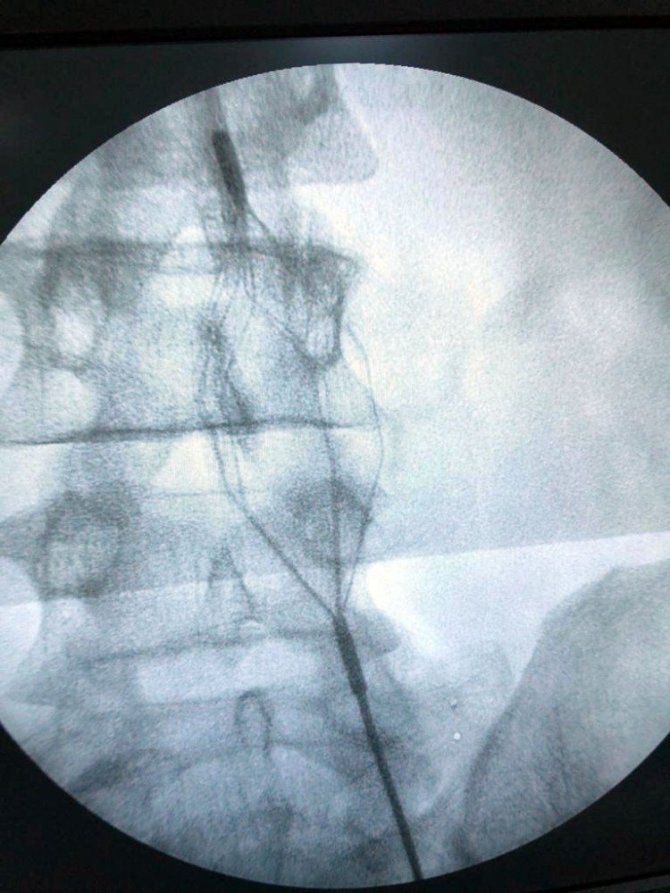

Hastanın yıllarca kullanmış olduğu ilaçlara rağmen sağlığına kavuşamamasına karşılık Türkiye’nin geliştirdiği 4 milli tıbbi cihaz ile birlikte (TPS, Mantis, Dovi ve Viper) sadece 2 saat süren bir cerrahi müdahale ile artık hasta ayağa kalkabiliyor. En son Bingöl Devlet Hastanesi’nden Op. Dr. Oktay Tüydeş ve Op. Dr. Abdurahman Muratoğlu tarafından, sol bacağında Trombüs (kanın bir atardamar ya da toplardamar içinde ya da bir organda pıhtılaşması) saptanan hastanın ameliyatı gerçekleştirildi. Gerçekleştirilen ameliyatta, hastanın vücudundan yaklaşık 350 cc, yani yarım kilogram pıhtı çıkartıldı ve hasta 2 gün içerisinde iyileşerek taburcu edildi. Riskli grupta yer alan bu ameliyatlar yalnızca Bingöl Devlet Hastanesi’nde değil artık Türkiye’nin 81 ilinde uygulanacak.